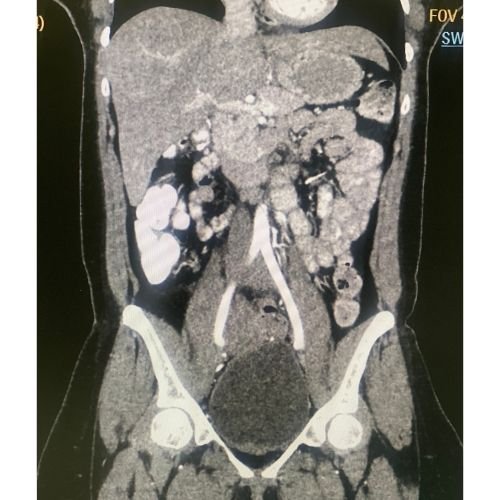

Realce Arterial Avanzado Tomografía computarizada aplicada

Programa de formación especializado en realce arterial en tomografía computarizada, enfocado en la integración adecuada de los parámetros técnicos, la fisiología del paciente y la correcta administración del medio de contraste. El curso incluye el manejo del inyector automático y las principales técnicas de sincronización del escaneo, con un enfoque práctico y clínico orientado a optimizar la calidad diagnóstica de los estudios arteriales.